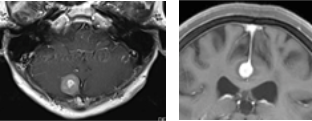

鞍結節部髄膜腫

鞍結節部髄膜腫とは、頭蓋底の奥深い場所にある骨の出っ張りに付着するように存在する髄膜腫です。その近くに視神経が接しているため、腫瘍を放置しておくとわずかに大きくなるだけで視神経を圧迫し始めます。手術で摘出しないと、そのまま失明の危険があります。この部位の髄膜腫はたとえ腫瘍の大きさが小さくても手術を勧めます。

特に視力低下・視野障害の自覚があれば、放置しておくと失明する可能性が高いため、手術を受けた方が良いと考えます。

(術前MRI)

(術後MRI)